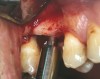

A 53-year-old female was referred for evaluation of a fracture of tooth No. 24. The tooth had been treated endodontically 5 years prior. The radiograph revealed a complete fracture of the tooth involving the crown (Figure 12). Tooth extraction and immediate placement of a an implant that was 10 mm in length and 3.75 in diameter was planned.

At the time of surgery, the tooth was extracted without harvesting any mucosal flap because the implant site was prepared by means of a pilot drill bur (Figure 13) and alternating osteotomes (Figure 14A and Figure 14B). The implant was positioned and showed primary stability. The implant was loaded 2 days after surgery. Then, splinted PFM crowns supported by custom gold abutments were delivered. At 6 months posttreatment, the radiograph revealed no bone resorption and the clinical result was optimal (Figure 15A and Figure 15B).

Figure 14A and Figure 14B Alternating osteotomes were used to prepare the implant site.